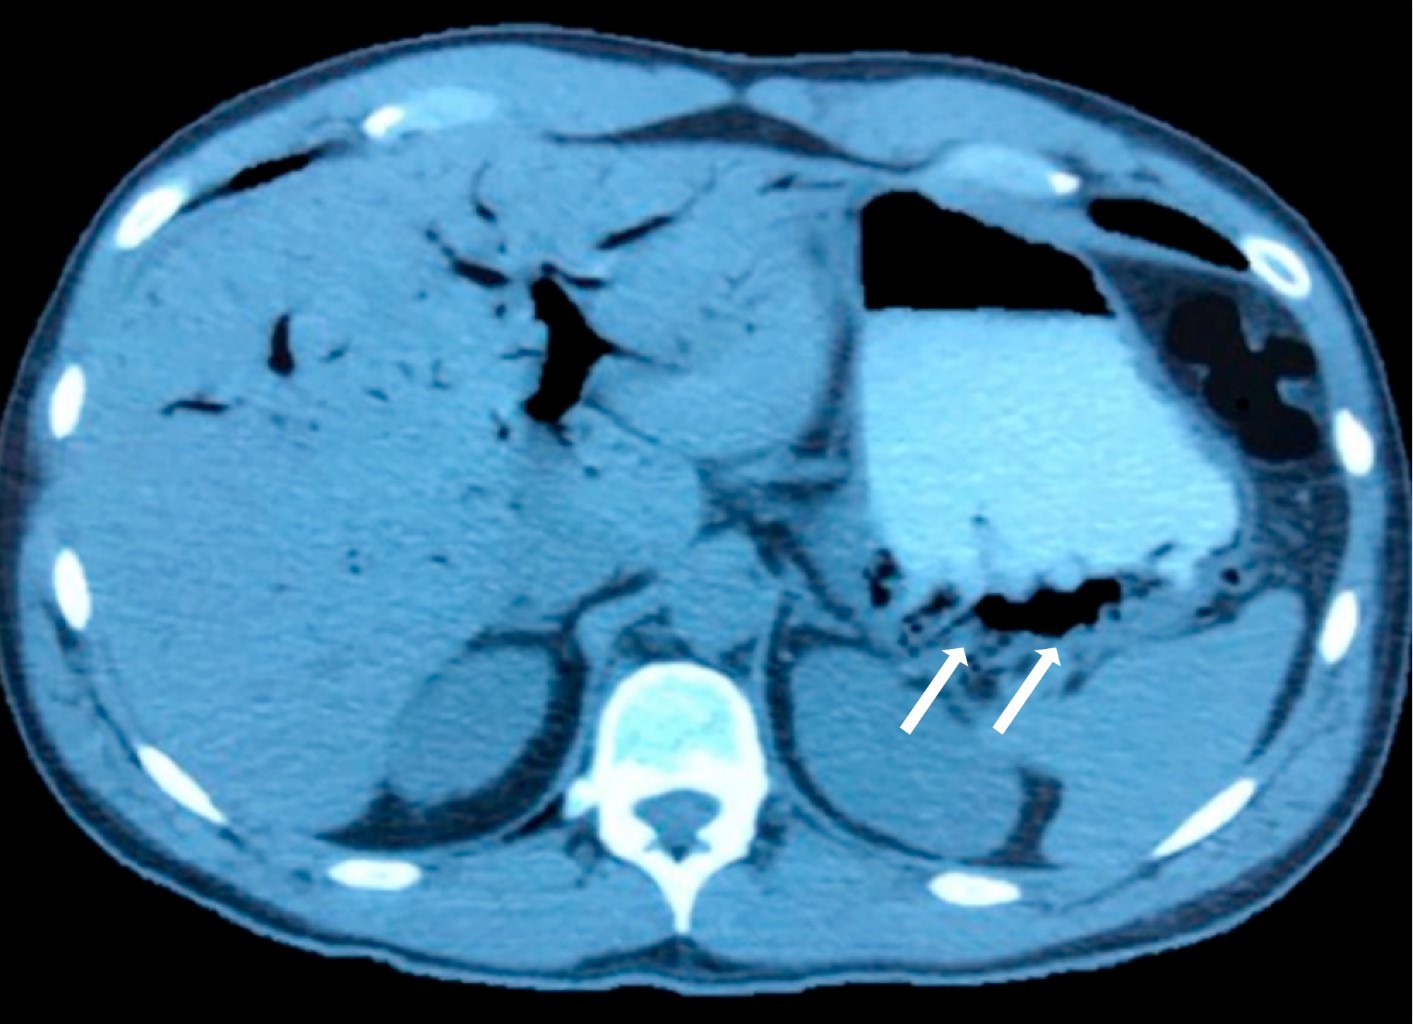

Paciente masculino de 40 años sin antecedentes de importancia que presentó un cuadro de inicio súbito con evacuaciones líquidas, dolor abdominal tipo cólico y malestar general. Se le encontró con signos vitales normales, deshidratación moderada y sin datos de irritación peritoneal o sepsis. Los laboratorios excluyeron leucocitosis, bandemia o alteraciones en las pruebas de función hepática. La radiografía simple de abdomen mostró dilatación de asas de intestino delgado y colon, así como niveles hidroaéreos dispersos, compatibles con íleo sin evidencia de obstrucción intestinal mecánica. El reporte radiológico describió "neumobilia", debido a la presencia de zonas radiolúcidas en el parénquima hepático (Figura 1). Esto motivó la decisión de realizar una tomografía computarizada, la cual se comenta como positiva para "neumobilia" (Figura 2) y, además, se reporta como posible causa la presencia de una "fístula colecistoduodenal", sin que existieran otros hallazgos que sustentaran estos diagnósticos. Sin una indicación clara, se decidió realizar una colangiopancreatografía retrógrada endoscópica (CPRE) que fue reportada como normal, sin alteraciones en la vía biliar. A las 24 horas, el paciente presentó dolor abdominal intenso, elevación de enzimas pancreáticas (amilasa 1,421 UI y lipasa 2,306 UI) y mal estado general. Se diagnosticó pancreatitis aguda leve según los criterios de Atlanta (APACHE II) y grado C según los de Balthazar. El paciente fue trasladado a otro hospital en donde se dio manejo médico a la pancreatitis y fue dado de alta siete días después, encontrándose en buen estado de salud hasta la fecha.

El caso clínico que presentamos ilustra dos problemas con los cuales los radiólogos y clínicos se pueden enfrentar: la inadecuada diferenciación radiológica entre neumobilia y gas portal, y el sobretratamiento de un paciente basado en un diagnóstico equivocado. En un análisis retrospectivo de los estudios radiológicos, se puede observar que las imágenes radiolúcidas son de predominio periférico (Figura 1) y que existe gas en la circulación venosa perigástrica (Figuras 2 y 3) y portal, mismos que se debieron haber atribuido al cuadro gastroenteral que presentaba el paciente. Esto hubiera evitado la pancreatitis que fue secundaria a una CPRE equivocadamente indicada. Así como en este caso, en la literatura existen ejemplos de abordajes terapéuticos erróneos debido a la confusión diagnóstica inicial. Es por eso que en esta discusión analizaremos los aspectos más relevantes sobre la diferencia clínica, diagnóstica y terapéutica entre neumobilia y gas portal.

Aspectos diferenciales del diagnóstico radiológico. Existen ciertos patrones radiológicos que pueden ayudar a establecer el diagnóstico diferencial entre neumobilia y gas portal; en la radiografía simple de abdomen la neumobilia se manifiesta con la presencia de imágenes radiolúcidas, dentro del parénquima hepático, con un patrón de distribución que semeja al árbol biliar, como ejemplo tenemos el "signo del sable", el cual es una zona radiolúcida ubicada a la derecha de la columna vertebral, a nivel del lóbulo izquierdo del hígado (gas en el conducto hepático izquierdo).12 En una tomografía el aire tiende a ser más central y estar a más de 2 cm de la cápsula hepática (debido a que la bilis fluye de la periferia hacia el hilio) con un patrón menos "enramado" o vascular.5 Si esto se complementa con ultrasonido, se puede apreciar cómo el gas biliar permanece estático.13 Cabe mencionar que la ausencia radiológica de neumobilia ha sido utilizada para predecir obstrucción de las prótesis biliares. Por otra parte, la imagen de gas portal, se define radiológicamente como la presencia de áreas de aspecto tubular con atenuación disminuida y localizadas hacia la periferia del parénquima hepático. Aunque el gas portal puede ser detectado en radiografías simples de abdomen, es mucho más fácil con la tomografía. Además, con el ultrasonido se logra apreciar cómo las burbujas de gas se desplazan en forma centrífuga hacia la periferia del hígado.